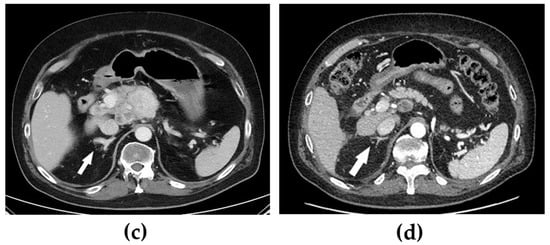

Several kinase inhibitors are available for the treatment of metastatic medullary thyroid cancer (Figure 2) [15]. Treatment with two of these, vandetanib and cabozantinib, were tested in our patient but were discontinued due to lack of effectiveness and side effects, respectively. In a study by Koehler et al., control over hypercortisolism was achieved in one patient with ectopic Cushing’s syndrome by using a tumour-targeted treatment with vandetanib and subsequently cabozantinib [7]. In another study, two patients with ectopic Cushing’s syndrome due to medullary thyroid cancer received vandetanib, but with inadequate control of the hypercortisolism, concomitant treatment with a cortisol-lowering agent was needed [16].

Figure 2.

Schematic summary of the effects of tyrosine kinase inhibitors for metastatic medullary thyroid cancer. Vandetanib and cabozantinib are multi-targeted inhibitors. Vandetanib is mainly an inhibitor of vascular endothelial growth factor receptor-2 (VEGFR2), epidermal growth factor receptor (EGFR), and RET tyrosine kinase. Cabozantinib is mainly an inhibitor of VEGFR2, RET tyrosine kinase, and tyrosine-protein kinase Met (c-MET). Selpercatinib is a selective RET tyrosine kinase inhibitor, making it less toxic and less likely to cause side effects.